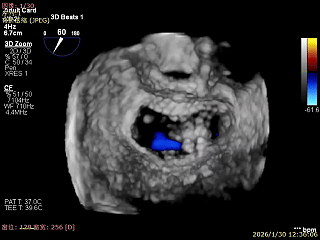

3D Enface下组织桥稳定无反流

夹子释放后,反流基本消失

LVOT切面可见主瓣二尖瓣术后反流基本消失

植入两枚夹子后二尖瓣平均跨瓣压差2mmHg